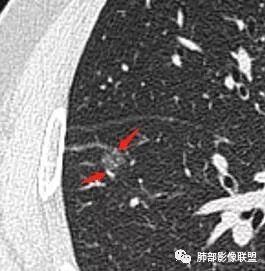

南边:

下面红色箭头这是月牙铲吗?

血管似有增粗

有增粗,联通、移动,高度怀疑Ca,常规抗炎后复查